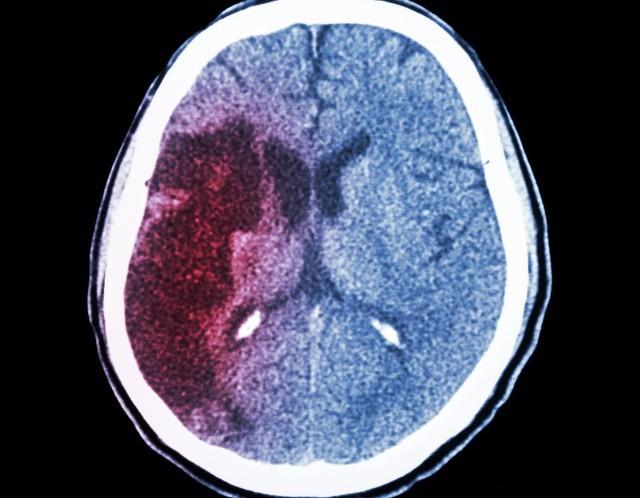

脑梗救治的“黄金时间窗”只有短短的4.5小时。在这段时间内,及时接受静脉溶栓治疗可以最大限度地挽救受损的脑组织,减少神经损伤,改善患者的预后。然而,每多耽误一分钟,就有190万个脑细胞死亡。时间,就是大脑。

为什么时间对脑梗救治如此关键?脑梗是由于脑部血管被血栓堵塞,导致局部脑组织缺血、缺氧,进而坏死。在发病初期,部分脑细胞虽然缺血,但尚未完全死亡。如果能在4.5小时内通过溶栓治疗恢复血流,这些濒临死亡的脑细胞还有可能存活,从而减少后遗症。